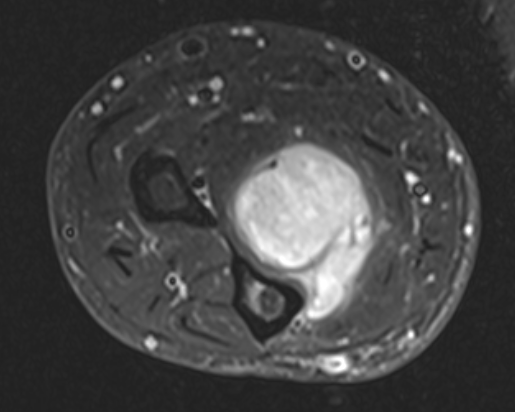

MRI

Anatomy / neurovascular involvement

Sarcoma medial thigh

Sarcoma anterior thigh